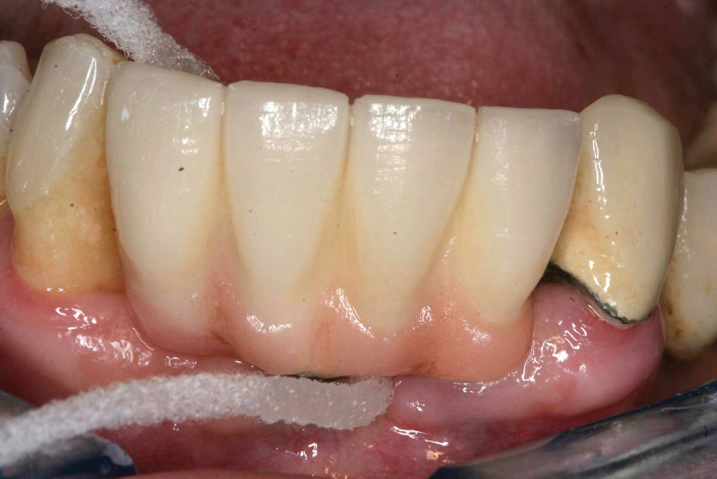

Fig 11. After thorough mechanical debridement and modification of the prosthesis to allow cleansing.

Figure 11

Preventive protocols must be instituted immediately after the installation of the definitive prosthesis and must focus on the importance of plaque control, both patient self-plaque control by strict home-based oral-hygiene practices and professional mechanical biofilm debridement at regular professional interventions, which must be customized to the patient’s risk profile.8 The efficacy of oral hygiene practices will depend on the ease of access to plaque control with both dental brushes and interdental devices, which depends mainly on the design of the prosthesis (Figure 6 through Figure 8). A cleansable implant-supported restoration, therefore, becomes a key factor in the primary prevention of peri-implant diseases. A recent systematic review on the efficacy of mechanical self-performed oral hygiene of implant-supported restorations reported a slight trend of superiority with the use of powered toothbrushes compared with manual.14

An important aspect of both professionally and patient-administered plaque removal is the cleanliness of the implant-supported restoration. A cohort study on 23 patients demonstrated that 74% of implants had no accessibility to proper oral hygiene and 48% of implants presenting with peri-implantitis were those that were not cleansable.17 The non-fitting or non-cleansable overhanging prostheses, therefore, should be considered iatrogenic factors that contribute to the development of peri-implantitis. Similarly, incorrectly positioned implants or foreign bodies such as impression material or excess luting cement can contribute to increased biofilm accumulation and hence favor the development of peri-implant diseases.10 Correction or elimination of these factors (eg, prosthesis removal and adjustment/replacement, if necessary) should be a principal component of the treatment of peri-implant mucositis (Figure 9 through Figure 11).